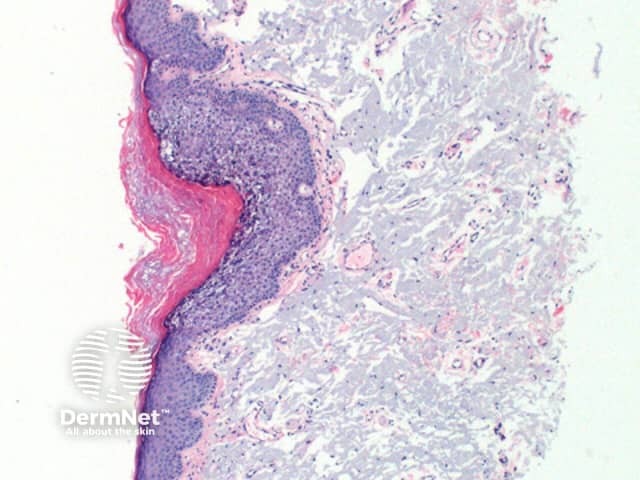

Low power view of histology of epidermolytic hyperkeratosis demonstrates hyperkeratosis and epidermal hyperplasia of varying degrees (Figure 1). The diagnostic features include a characteristic vacuolar degeneration with hypergranulosis of the stratum granulosum and stratum spinosum (Figures 2 and 3).